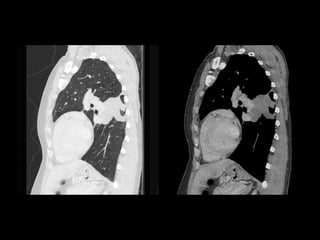

ASPERGILOMA

• No hay invasión tisular.

• Conglomerado de hifas con moco y detritus celulares.

• Se aloja en una caverna existente o bronquio ectásico.

• Tuberculosis y sarcoidosis.

• Generalmente son únicos.

• Hemoptisis.

ASPERGILOMA • No hayinvasión tisular. • Conglomerado de hifas con moco y detritus celulares. • Se aloja en una caverna existente o bronquio ectásico. • Tuberculosis y sarcoidosis. • Generalmente son únicos. • Hemoptisis. Spectrum of Pulmonary Aspergillosis: Histologic, Clinical, and Radiologic Findings Tomás Franquet, Nestor L. Müller, Ana Giménez, Pedro Guembe, Jesus de la Torre, and S. Bagué RadioGraphics 2001 21:4, 825-837